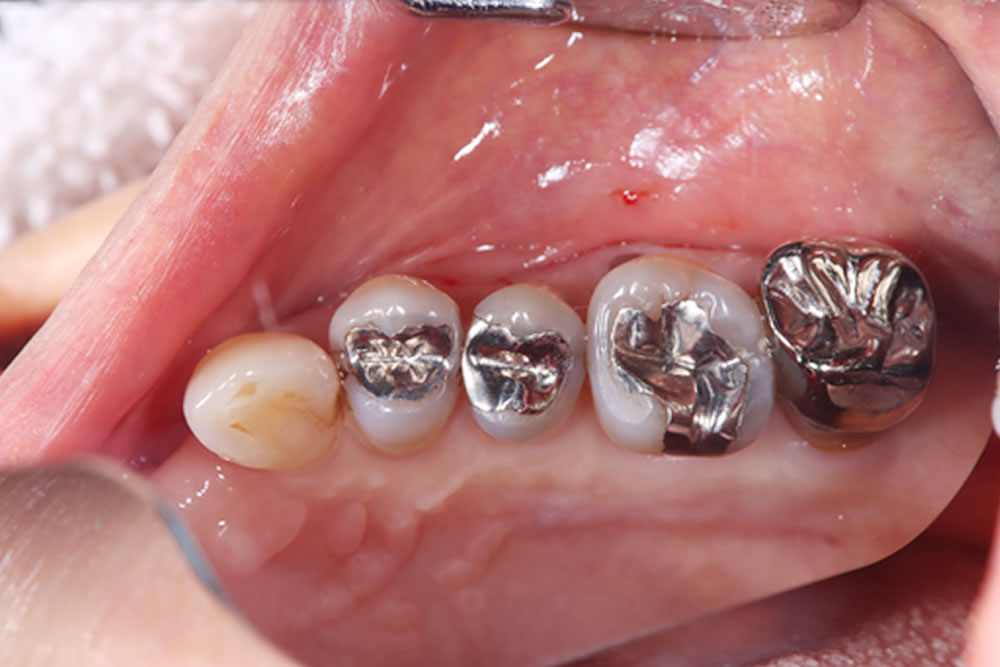

こちらの患者さまは、右下奥から2番目の歯が噛んだ時に痛いとの主訴で来院されました。

レントゲン写真にて、右下6番歯の歯根周囲に透過像を認めました。口腔内を確認したところ、メタルインレー下に二次う蝕を認めました。また、歯周ポケットは10mmと深く、歯根破折が疑われたため、補綴物を除去して精査することとなりました。

メタルインレーの除去

当該歯のメタルインレーを除去したところ、歯の内部に2次カリエス(虫歯の再発)を認めました。

う蝕検知液(虫歯部分に着色する薬液)を使用しながら、慎重に虫歯除去を行ったところ、遠心に歯根破折を確認しました。歯周ポケットが深かった部位と破折線が一致しており、このままつめ物を装着しても予後不良となる可能性があることを患者さまに説明したところ、抜歯とインプラントによる治療を希望されました。

また、他の銀歯の下にも複数の二次カリエスが認められたため、患者さまは口腔内全体の銀歯を除去し、再治療を行うことを希望されました。